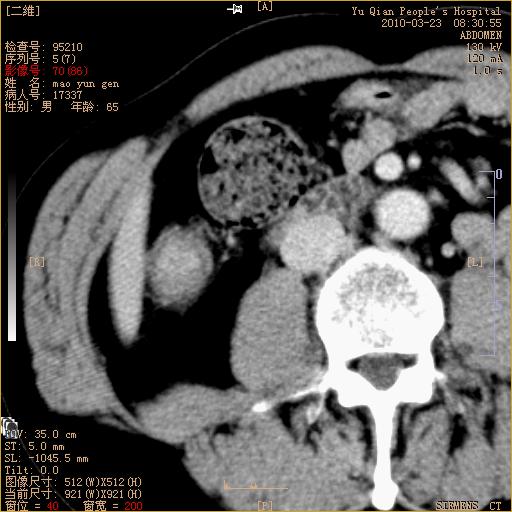

标题: CT25266:消瘦月余,前来肝部检查,请看看肠腔 [打印本页]

标题: CT25266:消瘦月余,前来肝部检查,请看看肠腔

肝区结肠占位,腺癌可考虑,建议肠镜活检。

升结肠肠壁增厚,不均强化,考虑升结肠腺癌可能性,建议肠镜检查。

1)考虑升结肠癌。2)右肾小囊肿。